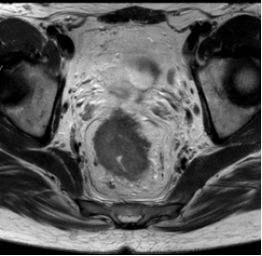

结直肠癌:CT常用于评估有无远处转移(如肝、肺转移)。而对于直肠癌,MRI具有独一无二的价值。它能以极高的软组织分辨率,清晰显示直肠肿瘤侵犯肠壁的深度、是否侵犯了直肠周围的系膜筋膜、以及系膜内有无可疑的淋巴结。这些信息对于判断能否进行保肛手术、是否需要术前放化疗等,提供了最直接的影像学证据。

图2 直肠癌侵犯前方系膜筋膜(箭头处),可以先化疗减瘤后再行手术